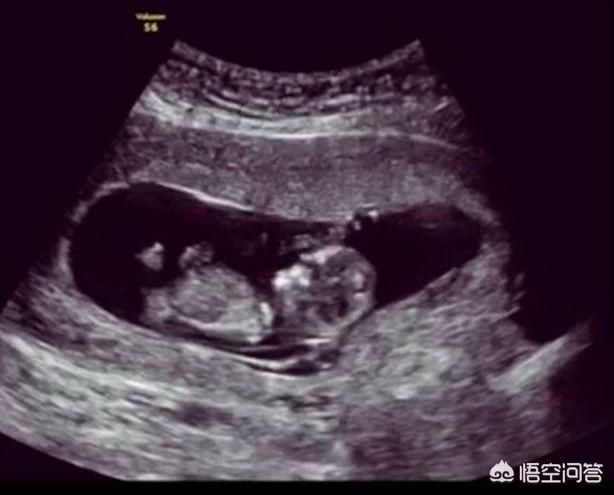

Au cours de la grossesse, un examen échographique sera effectué, car de nombreuses mères enceintes auront ce doute, c'est-à-dire qu'au cours de l'examen de la grossesse, on procédera à un examen échographique plus multidimensionnel, tridimensionnel et quadridimensionnel. En cas d'inquiétude supplémentaire pour elles-mêmes et leur fœtus, le dépistage du syndrome de Down, l'amniocentèse et d'autres tests plus délicats et plus détaillés sont utilisés.

Selon cette comparaison, pendant la grossesse, même si l'examen échographique est performant, certaines maladies du fœtus doivent encore être examinées plus en détail par d'autres éléments, et il est difficile d'obtenir une totale tranquillité d'esprit en se contentant de l'examen échographique.

Dans ce cas, est-il encore nécessaire de faire une échographie pendant la grossesse ? En fait, je voudrais rappeler à toutes les futures mamans que l'échographie pendant la grossesse est tout à fait nécessaire. Tout comme il existe des spécialités, de nombreux examens pendant la grossesse ont leurs propres responsabilités.